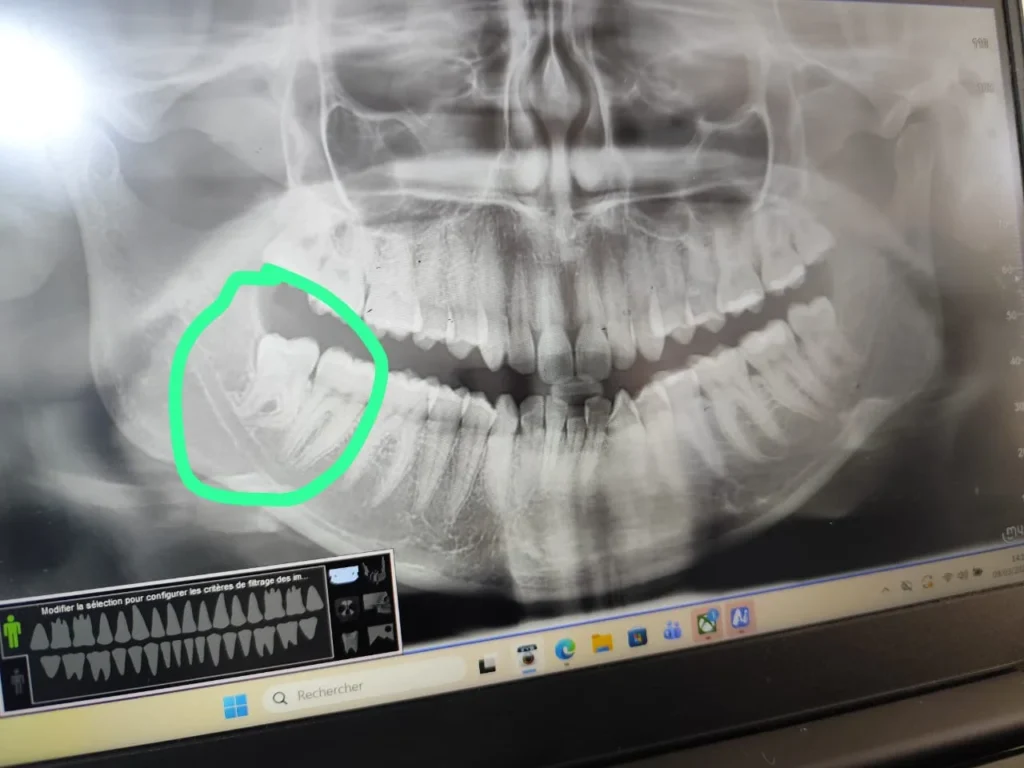

Bonjour,D’après votre description et la radiographie, il s’agit très probablement de dents de sagesse incluses (surtout en bas à droite, comme entouré sur l’image), ce qui explique la douleur plus importante de ce côté.

ale.

Donc, pEn général :

Lorsque la dent est bien sortie et accessible → l’extraction est simple (normale).

Lorsqu’elle est incluse, mal positionnée ou partiellement sortie (comme dans votre cas) → l’extraction est chirurgi

cour vos dents de sagesse, il est très probable que l’intervention soit chirurgicale, surtout pour celles du bas.